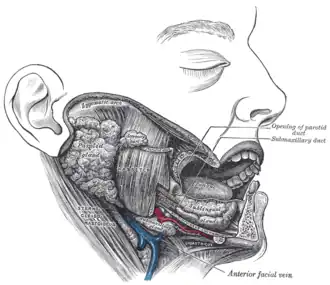

Dissection, showing salivary glands of right side. (Parotid duct visible at center.) | |